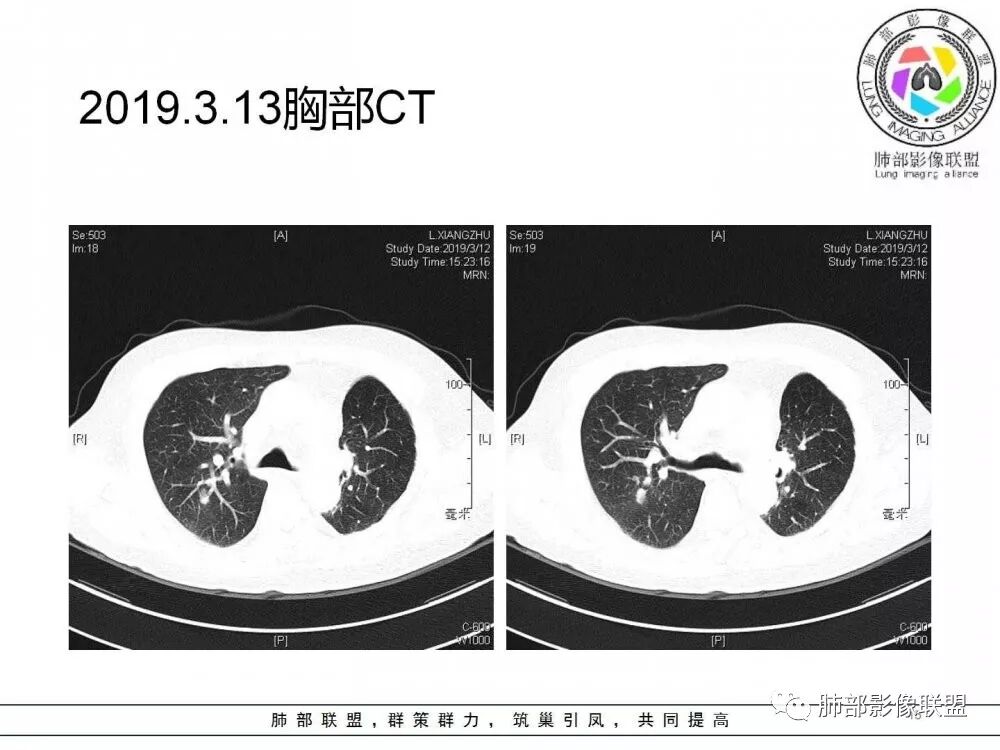

右肺上叶后段实性结节,部分边缘磨玻璃,周围可见多发小结节,病灶逐渐进展,临床有肺癌病史、IgG4相关病变、激素长期使用史,考虑1、隐球菌;2、肺癌复发;3、IgG4相关性肺改变,病变局限,应该不符合。

右肺上叶后段多发实性结节,边缘收缩,葫芦兄弟,临床有激素治疗史,考虑隐球菌。

肺癌病史,长期激素使用史,IgG4相关病史,治疗有抗癌和激素治疗,肺部多发胸膜下小结节,边缘模糊,有些结节有进展,葫芦兄弟,考虑隐球菌。

右肺上叶后段实性结节,周围可见多发小结节,病灶逐渐进展,临床有肺癌病史、IgG4相关病变、激素长期使用史,考虑1、隐球菌;2、肺癌复发;3、IgG4相关性肺改变

肺部病灶从2月份就开始有了,应该最早说是1月7号就有了,到3月13号稍微增大一点,到后面几乎就没变化了,到5月份好像稍微大一些,炎性肯定是炎性,就是这个炎性是到底什么病变呢?其实本没变化,它特点一个是在叶裂上,跟血管关系密切,但是病灶边缘稍收缩,病灶这么没有太大变化,我还是支持炎性病变。